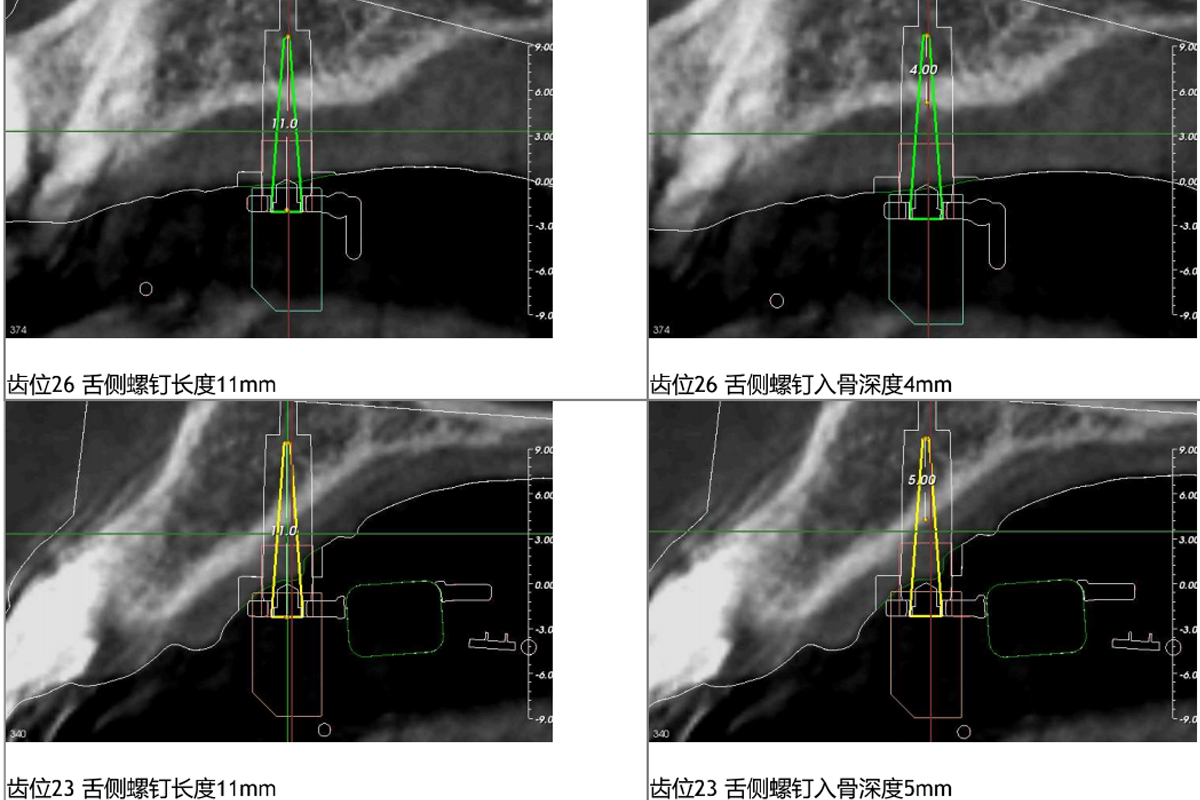

客制化骨性扩弓器(套),这是一种微种植钉辅助快速上腭扩展装置,可针对上颌牙弓横向发育不足(牙弓狭窄)的患者开展骨性扩弓,尤其是青春发育期后及腭中缝已经闭合的成人患者。该技术利用4颗种植支抗钉植入上颌骨腭侧骨板, 通过微种植钉传递矫形力,以上颌骨作为支抗骨,与腭中缝、翼腭缝等结构所产生的阻力相抗衡,当矫形力大于阻力时,腭中缝便会打开,从而实现上颌骨骨性扩弓。此装置最大程度的增加骨性扩弓的效果,并且最大限度的减少了常规扩弓可能带来的副作用,如后牙颊倾现象,牙槽骨高度降低,牙槽骨复发、开裂等副作用。

2、我们公司跟据上颌骨的条件设计摆放骨钉的位置。

3、与医生确定骨钉的尺寸。(骨钉需医生自备提供)。

4、医生确认骨钉的位置。